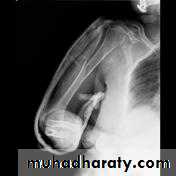

Pain, bruises at site of fracture, radial nerve examination before &after treatment by extension of metacarpo-phalangeal joints.Holstein-Lewis fracture :

a spiral fracture of the distal one-third of the humeral shaft commonly associated with neuropraxia of the radial nerve (22% incidence due to entrapment of the radial nerve between fracture site),& need urgent open reduction & internal fixation with freeing of the nerve.

Type of fixation either by plate and screws or intramedullary nail(in closed fracture) while in open fracture using external fixation with antibiotic cover, ATS and wound debridement and later on either secondary suture of the wound or skin graft in case of skin and soft tissue loss.